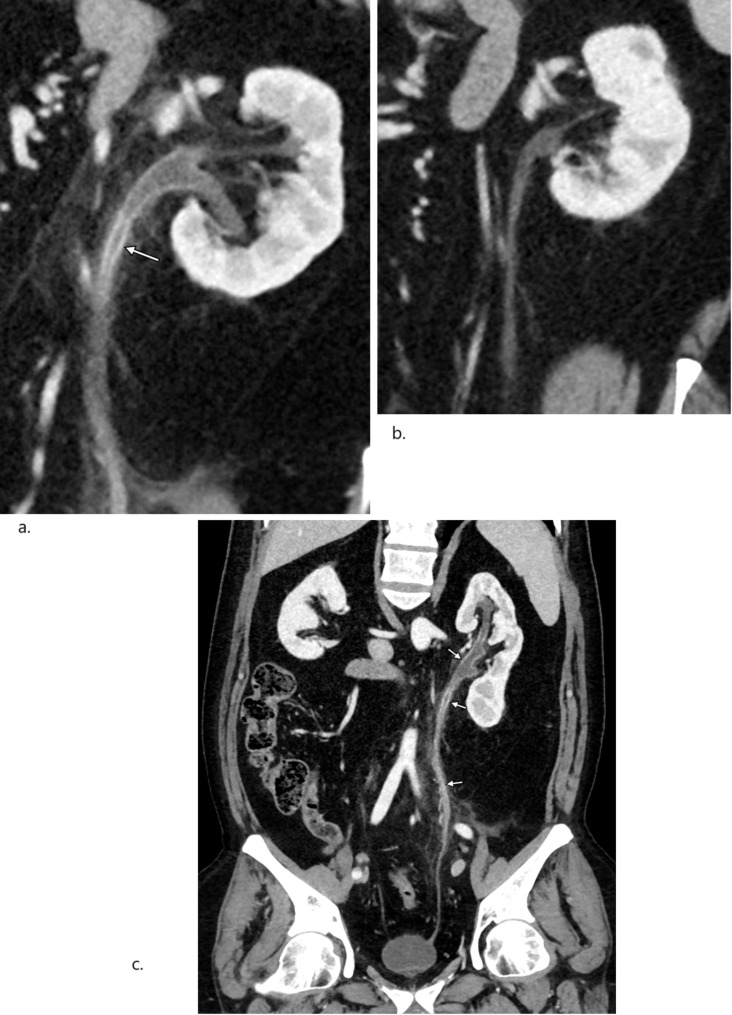

背景:卡巴他赛(cabazitaxel, CBZ)是转移性去势抵抗性前列腺癌(mCRPC)患者主要有效的治疗选择之一。膀胱炎和血尿是与CBZ治疗相关的最显著的非血液学不良事件。但由于cbz引起的输尿管炎的患病率尚未得到深入研究,因此进行了病例系列调查,以强调该疾病的临床相关性和潜在的治疗方案。病例介绍:2014年6月至2024年5月,在Vejle医院肿瘤科诊断为mCRPC的354例患者接受了CBZ治疗。共有36例患者(10%)出现输尿管炎样症状,表现为骨盆、下腹部或侧腹不适,伴或不伴血尿。36例患者中有29例(80%)存在输尿管改变的影像学证据,部分患者伴有肾积水/输尿管积水。在CBZ治疗之前,36例患者中有7例(19%)记录了骨盆或下腹部的放疗。各种镇痛药和剂量调整被考虑用于治疗cbz引起的输尿管炎,治疗停止产生最有利的结果。结论:CBZ治疗过程中发生输尿管炎是临床中被低估的不良反应。血尿和肾积水/输尿管积水是最常见的并发症。止痛剂和减少剂量都应该考虑治疗,而某些个体可能需要停止治疗。

Case presentation: Between June 2014 and May 2024, 354 patients diagnosed with mCRPC were treated with CBZ at the Department of Oncology, Vejle Hospital. A total of 36 patients (10%) exhibited ureteritis-like symptoms, presenting with discomfort in the pelvis, lower abdomen, or flanks, with or without hematuria. Radiological evidence of ureter changes was present in 29 out of 36 individuals (80%), along with hydronephrosis/hydroureter in some patients. Prior to therapy with CBZ, radiation to the pelvis or lower abdomen was documented in 7 out of 36 patients (19%). Various analgesics and dosage modifications were considered for the therapy of CBZ-induced ureteritis, with treatment discontinuation yielding the most favorable results.